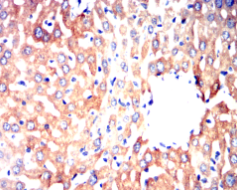

CYP3A4 Mouse Monoclonal antibody[3H8D2]

IHC    1/100 - 1/500